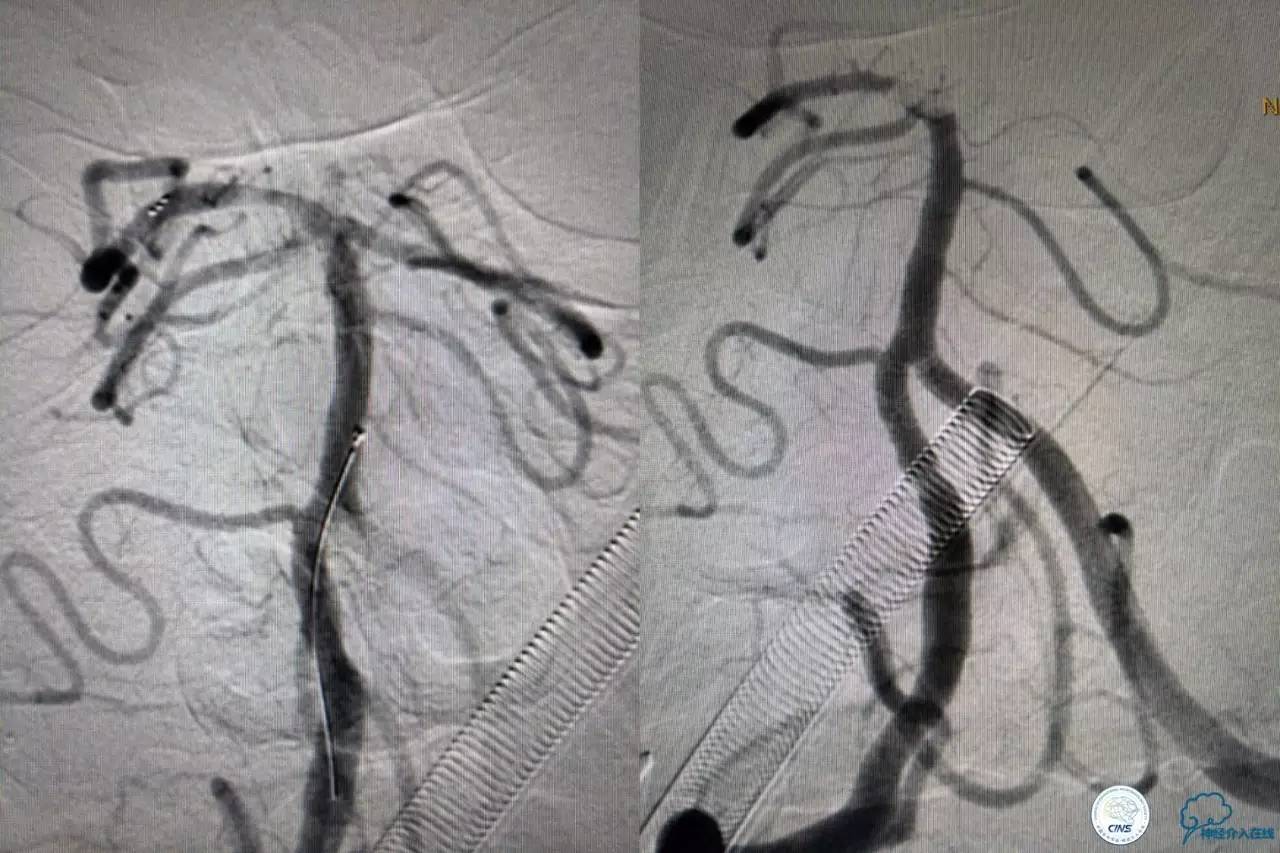

solitaireAB4-20mm支架取栓。

第三次取栓后,左侧大脑后动脉开通,但是栓子再次栓塞右侧大脑后动脉,血栓在基地动脉顶端来回左右摆动,下一次,怎办?血栓负荷太多,可以使用solumbar技术,可以没有颅内导管,没办法,换用更大的支架6-20mm,但费用增加不少,与家属沟通后同意使用,第四次取栓:

血栓负荷还是很大,左侧大脑后再通,但右侧大脑后又闭塞,只能第五次取栓,支架放到右侧大脑后动脉更远。

好大的血栓,支架释放后,血管无复流,拉一把!

4.血栓负荷较重可选择最新技术,solumbar技术(支架取栓+导管抽吸)或双支架技术(没办法时)。